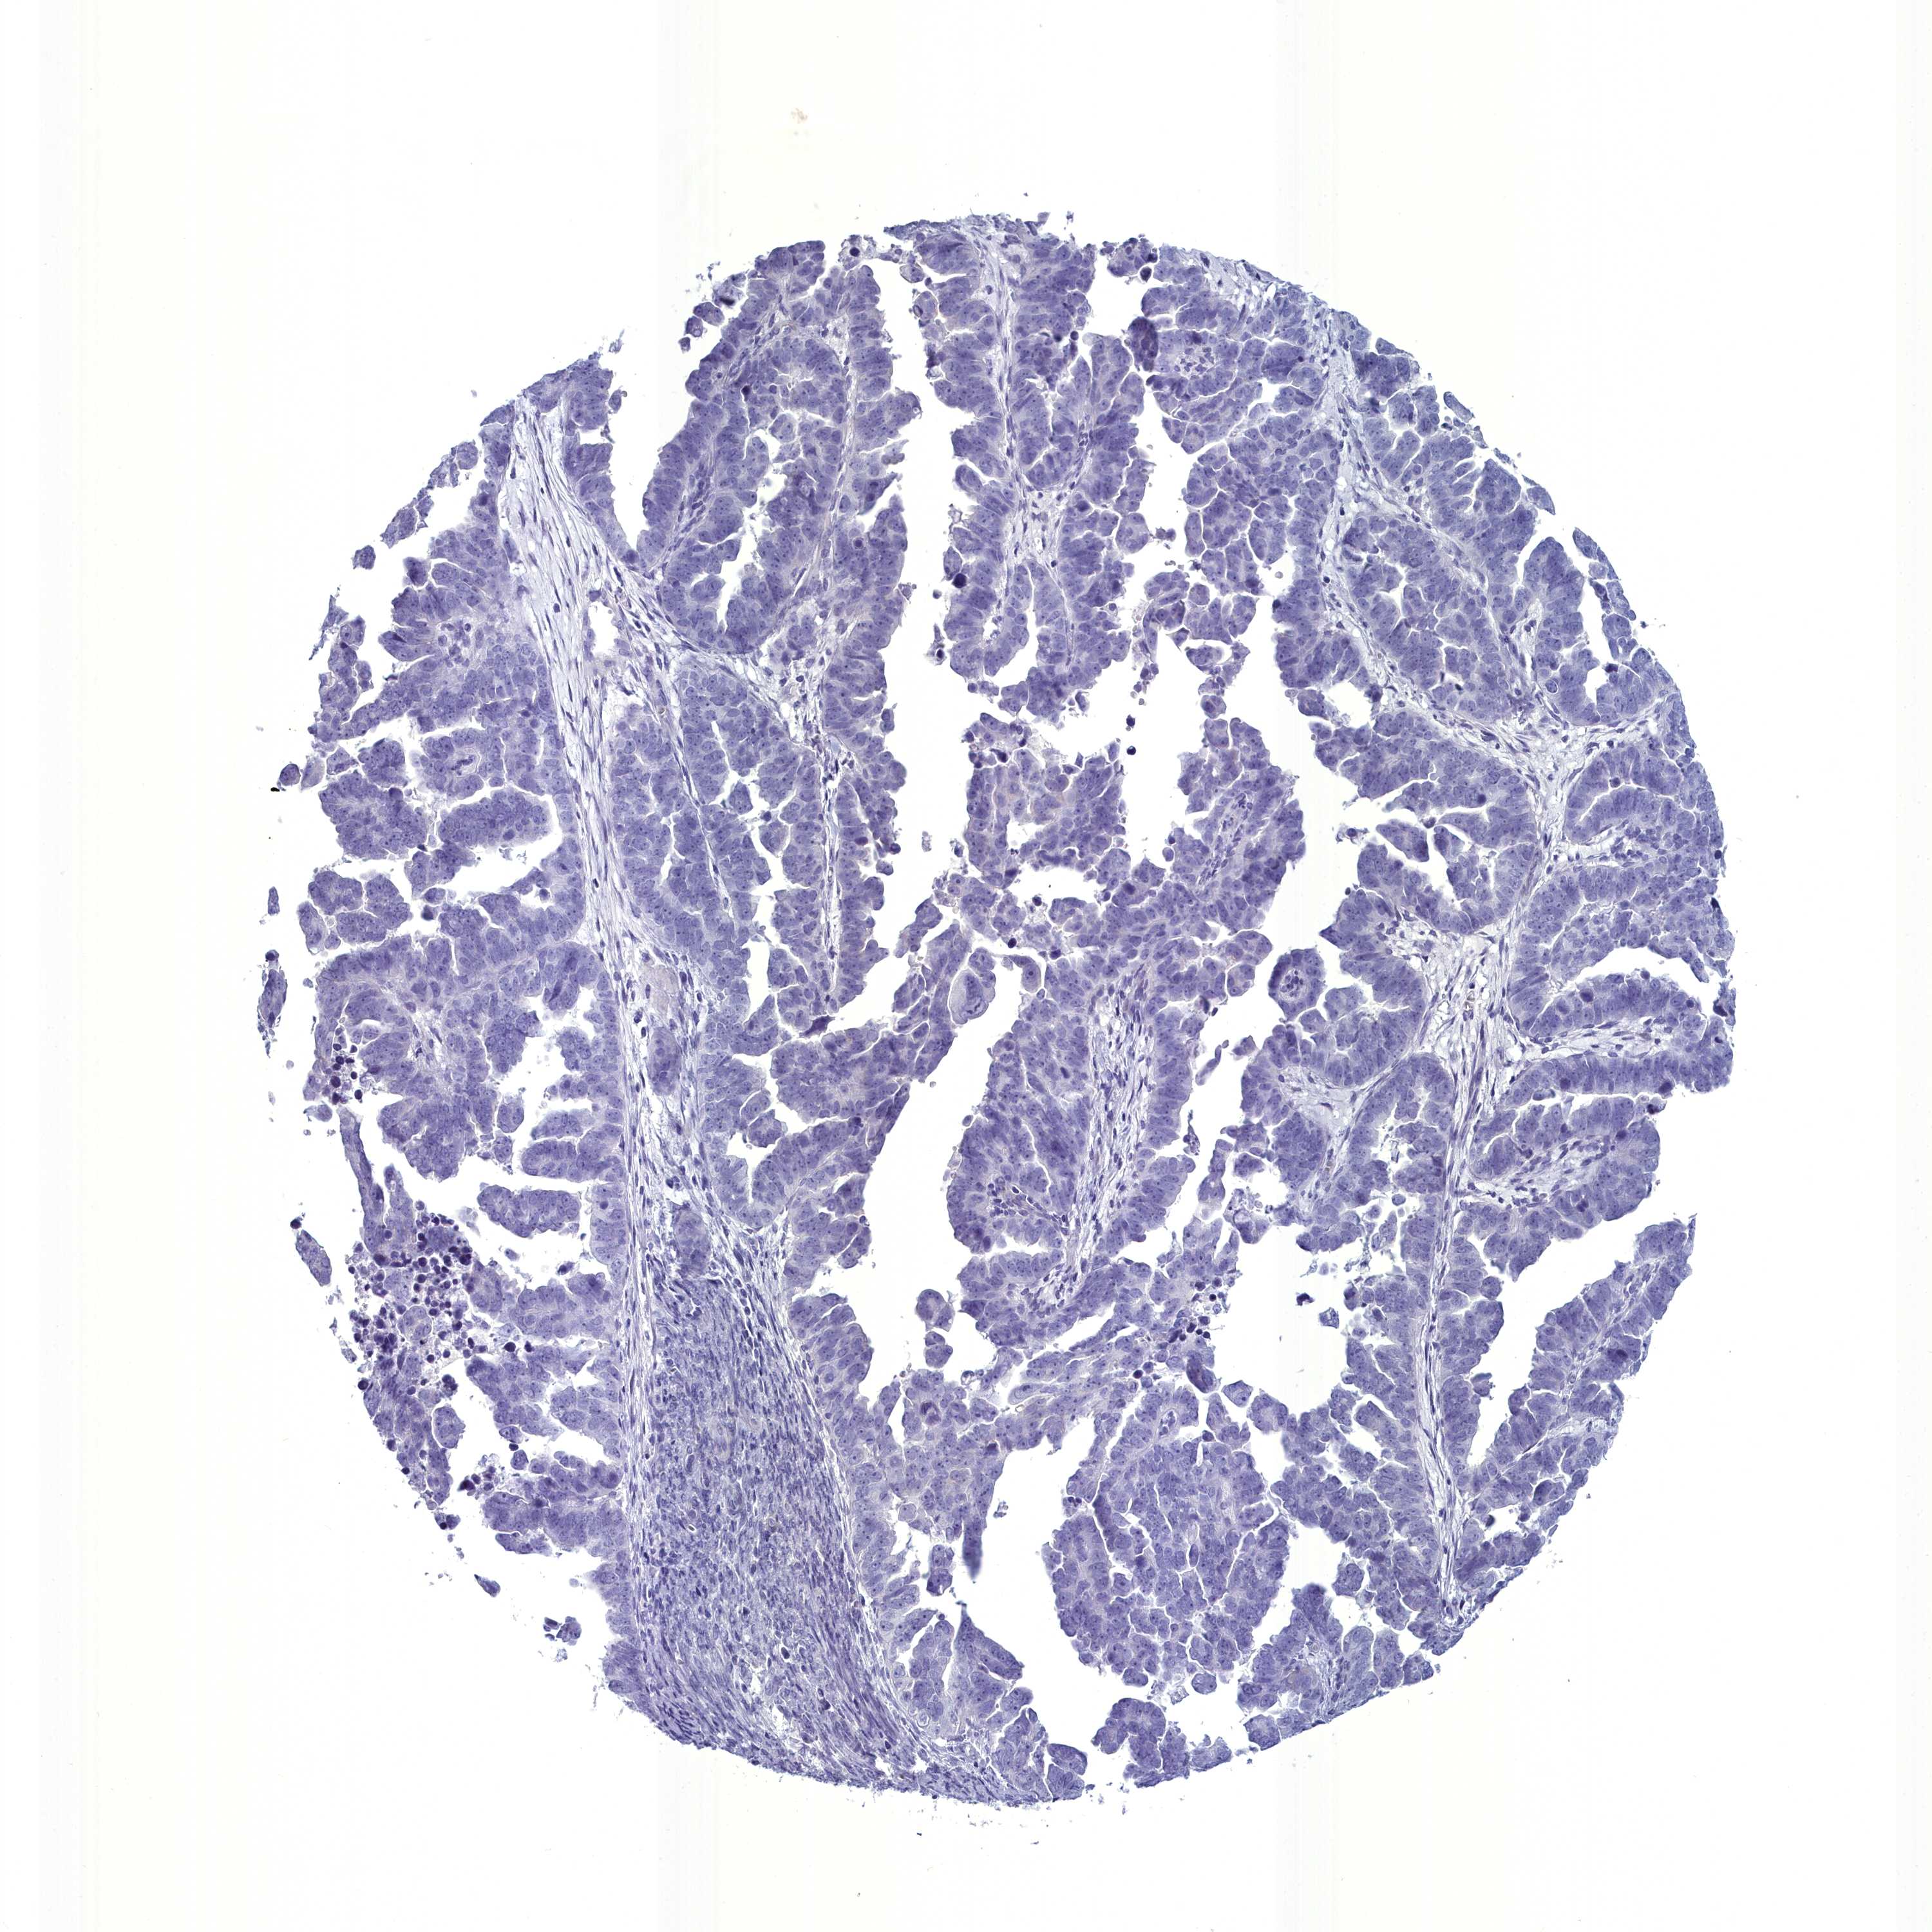

ENDOMETRIAL CANCER - Protein expressioni

A mouse-over function shows sample information and annotation data. Click on an image to view it in a full screen mode. Samples can be filtered based on level of antibody staining by selecting one or several of the following categories: high, medium, low and not detected. The assay and annotation is described here.

Note that samples used for immunohistochemistry by the Human Protein Atlas do not correspond to samples in the TCGA dataset.

Antibody stainingi

Antibody staining in the annotated cell types in the current human tissue is reported as not detected, low, medium, or high, based on conventional immunohistochemistry profiling in selected tissues. This score is based on the combination of the staining intensity and fraction of stained cells.

Each image is clickable and will lead to virtual microscopy that enables deeper exploration of all samples and also displays staining intensity scores, fraction scores and subcellular localization as well as patient and tissue information for each sample.

Antibody HPA039061

Antibody HPA039062

Antibody CAB015442

Antibody CAB022600

Staining

High

Medium

Low

Not detected

Intensity

Strong

Moderate

Weak

Negative

Quantity

>75%

75%-25%

<25%

None

Location

Nuclear

Cytoplasmic/membranous

Cytoplasmic/membranous,nuclear

Adenocarcinoma, NOS